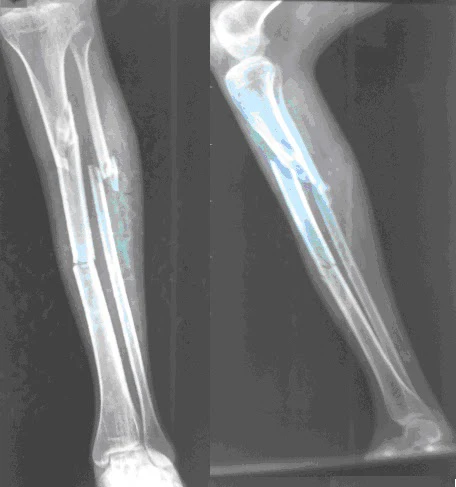

Gãy xương cẳng chân. Ảnh minh họa